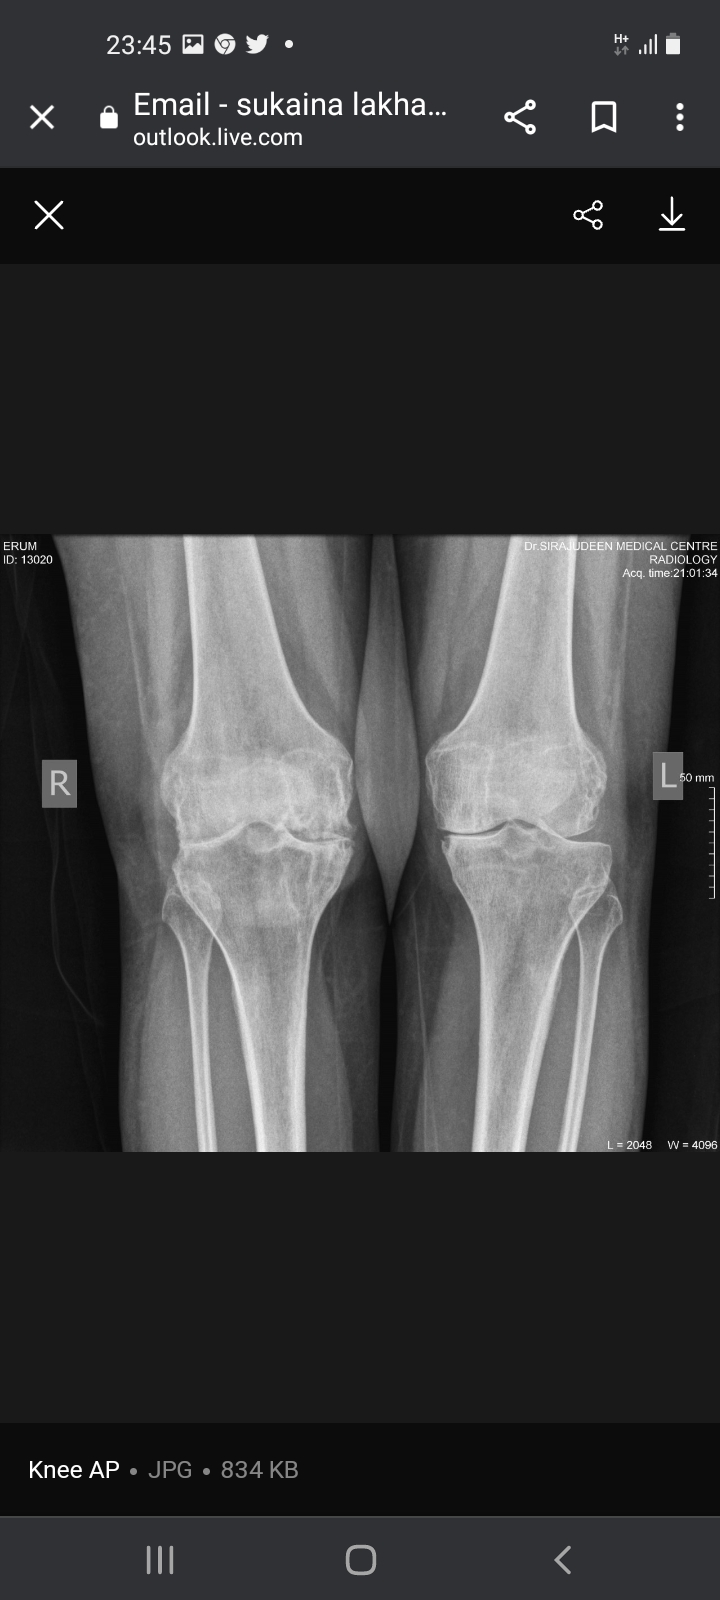

Not sure which treatment you are referring to. the Xrays show quite a bit of damage for someone who is just 40 yrs old. I suspect the patient may have inflammatory arthritis causing this. for this she should consult a qualified Rheumatologist for specialist treatment

I agree with Dr. Ashar, you are too young to have these x rays. See a rheumatologist soon.